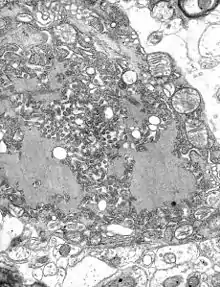

Viral encephalitis can occur either as a direct effect of an acute infection, or as one of the sequelae of a latent infection. The majority of viral cases of encephalitis have an unknown cause, however the most common identifiable cause of viral encephalitis is from herpes simplex infection.[8] Other causes of acute viral encephalitis are rabies virus, poliovirus, and measles virus.[9]